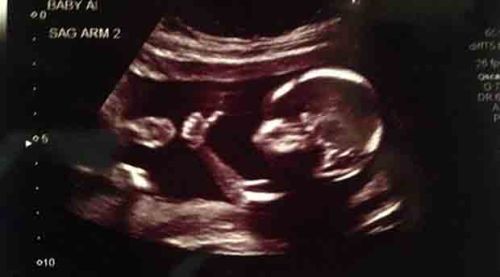

نشرت صحيفة "دايلي ميل" البريطانية صورة تم تداولها على مواقع التواصل الإجتماعي، تُظهر جنيناً في شهره التاسع وهو يرفع إبهامه في إشارة "Like" وكأنه يحاول طمأنة والديه عن صحته وأن معنوياته مرتفعة.

وذكرت الصحيفة أن "الوالد براندسون هوبكينز، الذي لم يتم ذكر جنسيته، لم يتوقع أن صورة الأشعة التي نشرها لجنينه ستحقق شعبية واسعة".

وفيما شكك البعض بمصداقية الصورة معتبرين أنها معدلة على برنامج الـ"Photoshop"، أكد هوبكينز أن "الصورة حقيقية ولم يتم تعديلها"